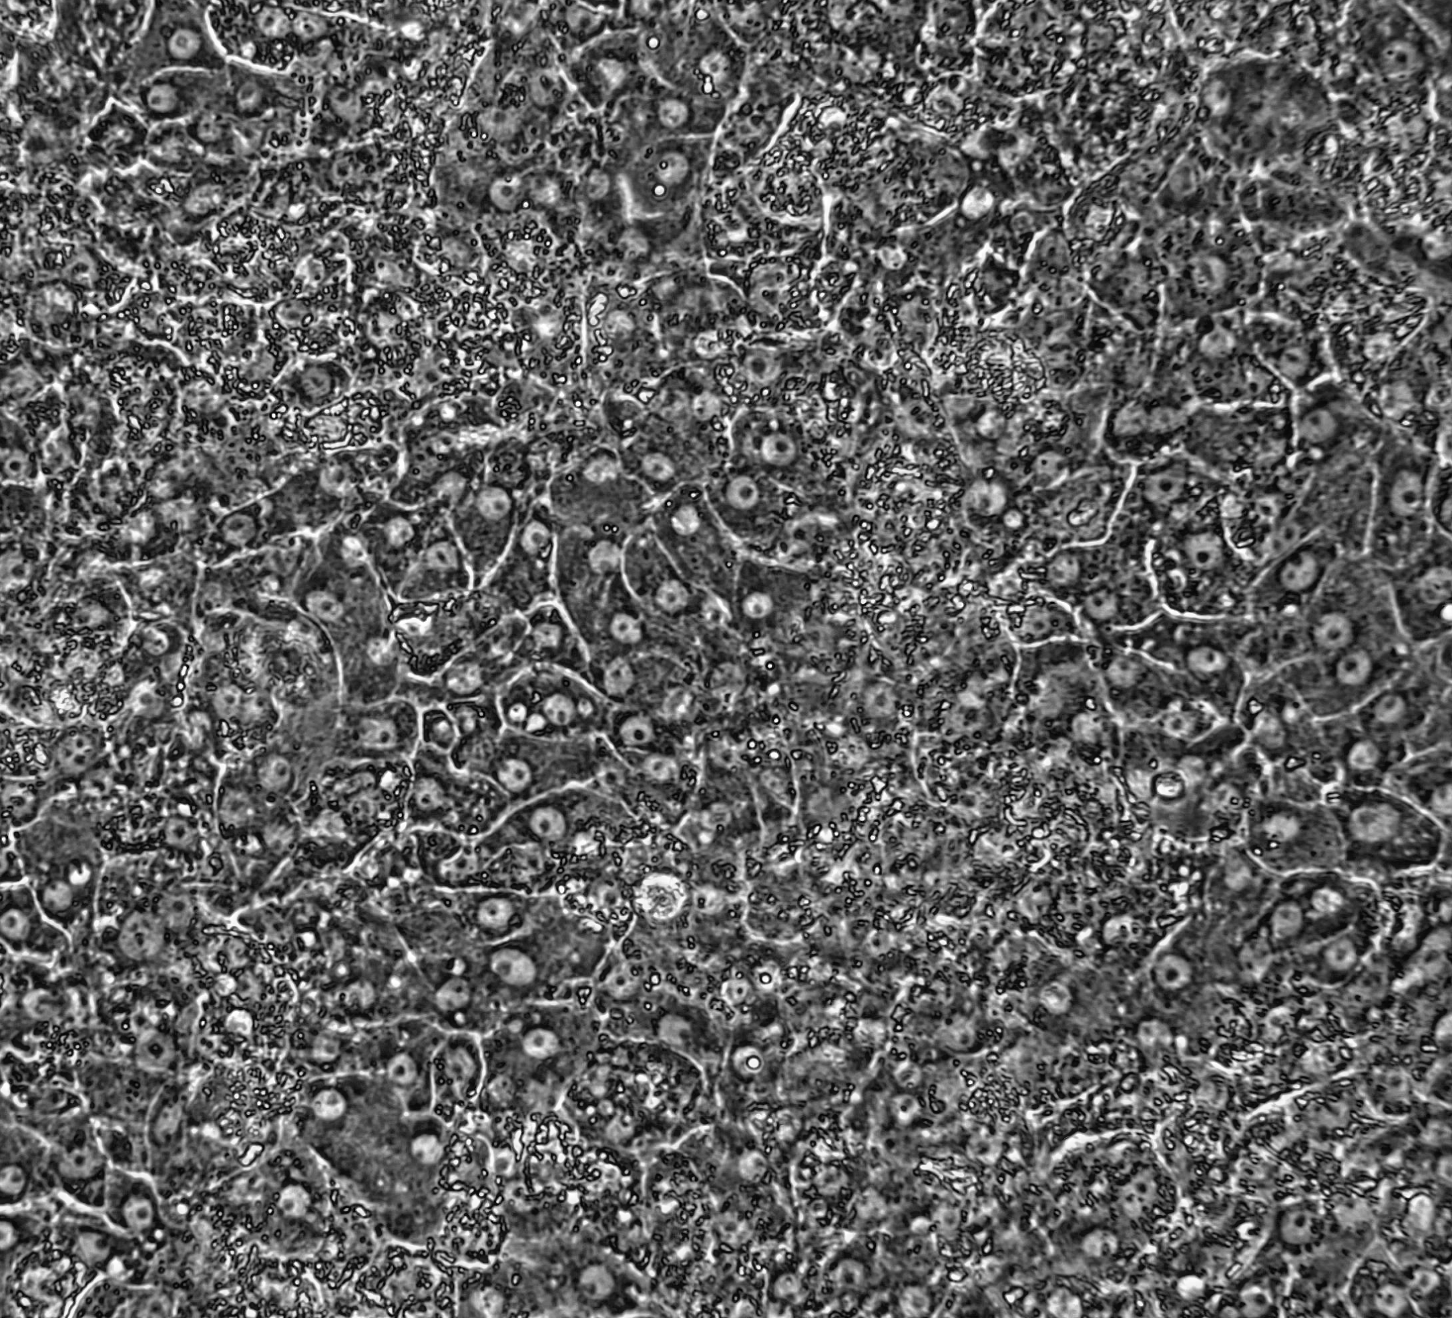

ioHepatocytes (Discovery Research), powered by opti-ox deterministic cell programming, deliver built-in batch-to-batch consistency for reproducible data. These highly characterised hepatocytes display a cobblestone morphology, prominent nuclei and expression of core hepatocyte markers from day 4.

ioHepatocytes_Discovery_Research_D14_morphology